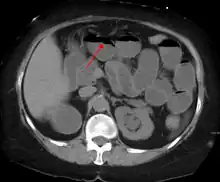

A small bowel obstruction as seen on CT

Small bowel dilation on CT scan in adults[11]

<2.5 cm Non-dilated

2.5-2.9 cm Mildly dilated

3-4 cm Moderately dilated

>4 cm Severely dilated